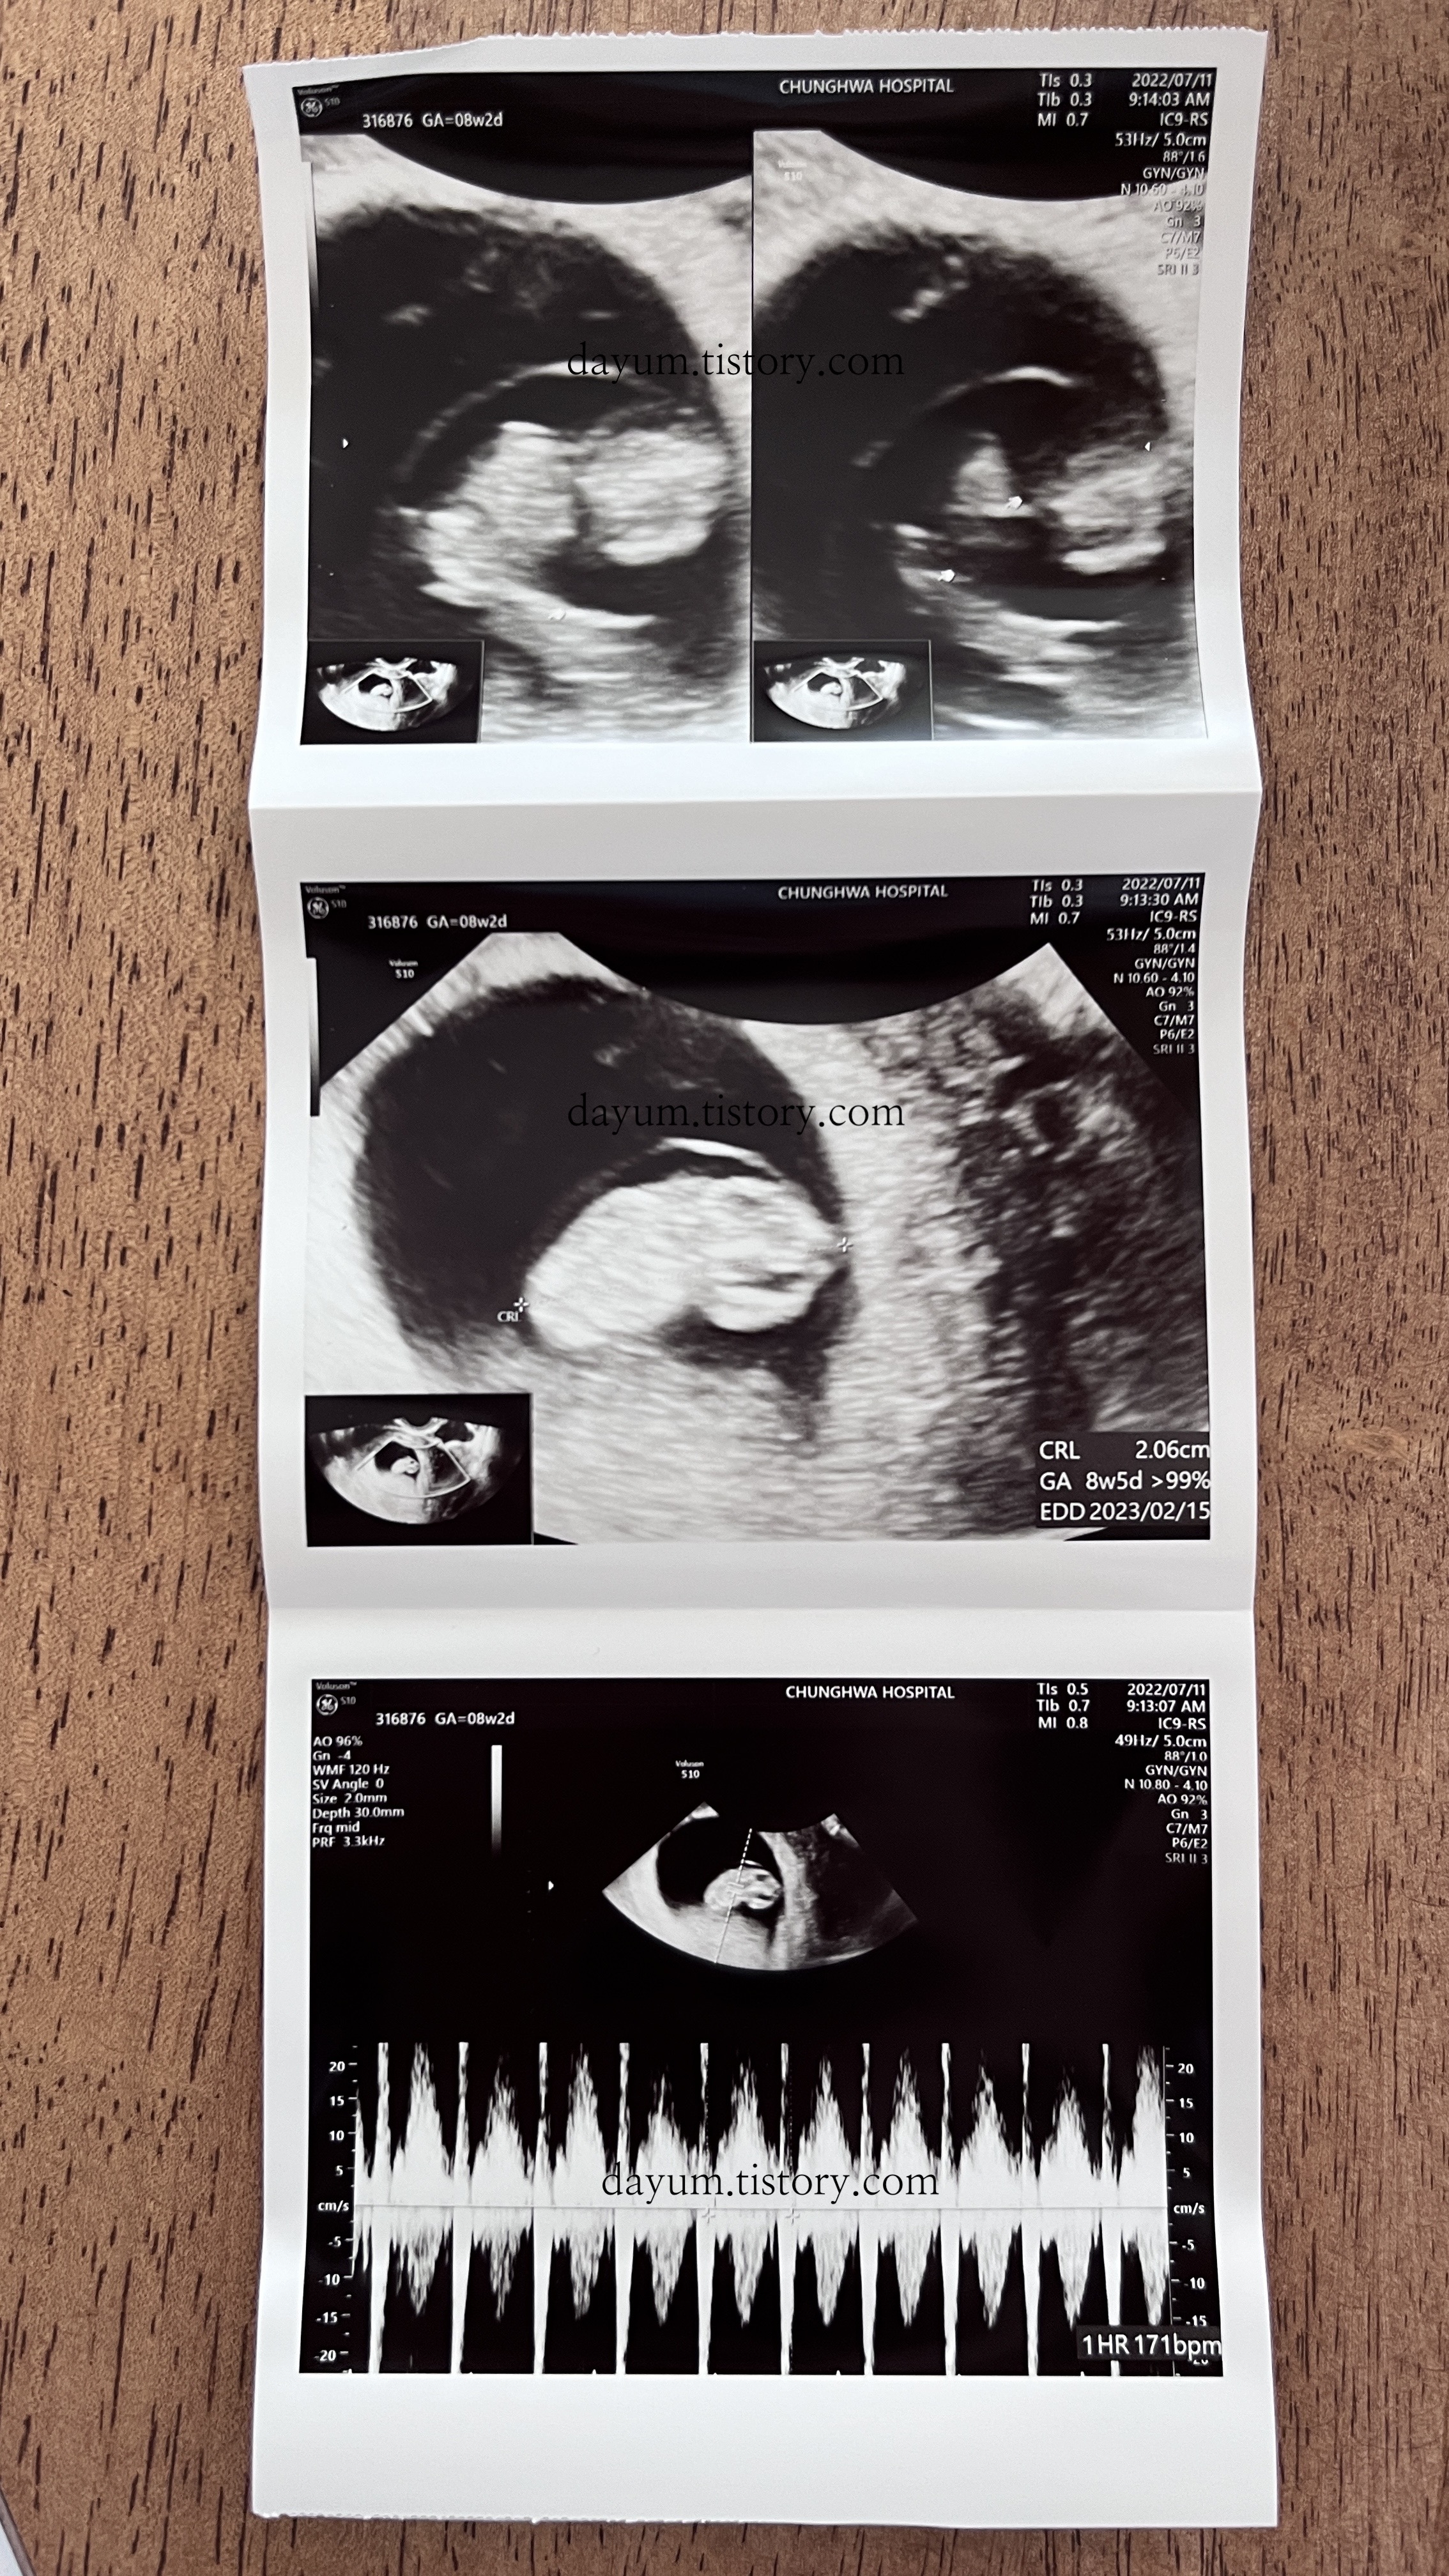

6주 2일과 8주 2일의 초음파 사진 차이

0.53cm의 크기에 심박수는 118bpm / 2.06cm의 크기에 심박수는 171bpm

2주 동안 1.6cm정도 자랐다.

8주 2일이지만 8주 5일 정도의 크기라고 한다.

탯줄과 팔, 다리가 생겼다.

이맘때쯤 볼 수 있는 젤리곰을 기대했지만 각도가 안나와서 젤리곰은 보지 못했다.

젤리곰은 아니고 강낭콩... 2등신...